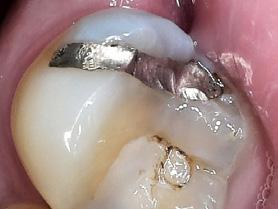

Dental hygienists independently utilize digital scanning for education and motivation. Not only can the clinician educate the patient with the images, but the patient has a visual that is easily understood. These images contain powerful visuals of attrition, fractured teeth, abfraction, gingival recession, overjet, and crowding.4 Biofilm can be displayed after the application of disclosing solution.5 Separate photos are not required to capture the biofilm present when using digital scanning.